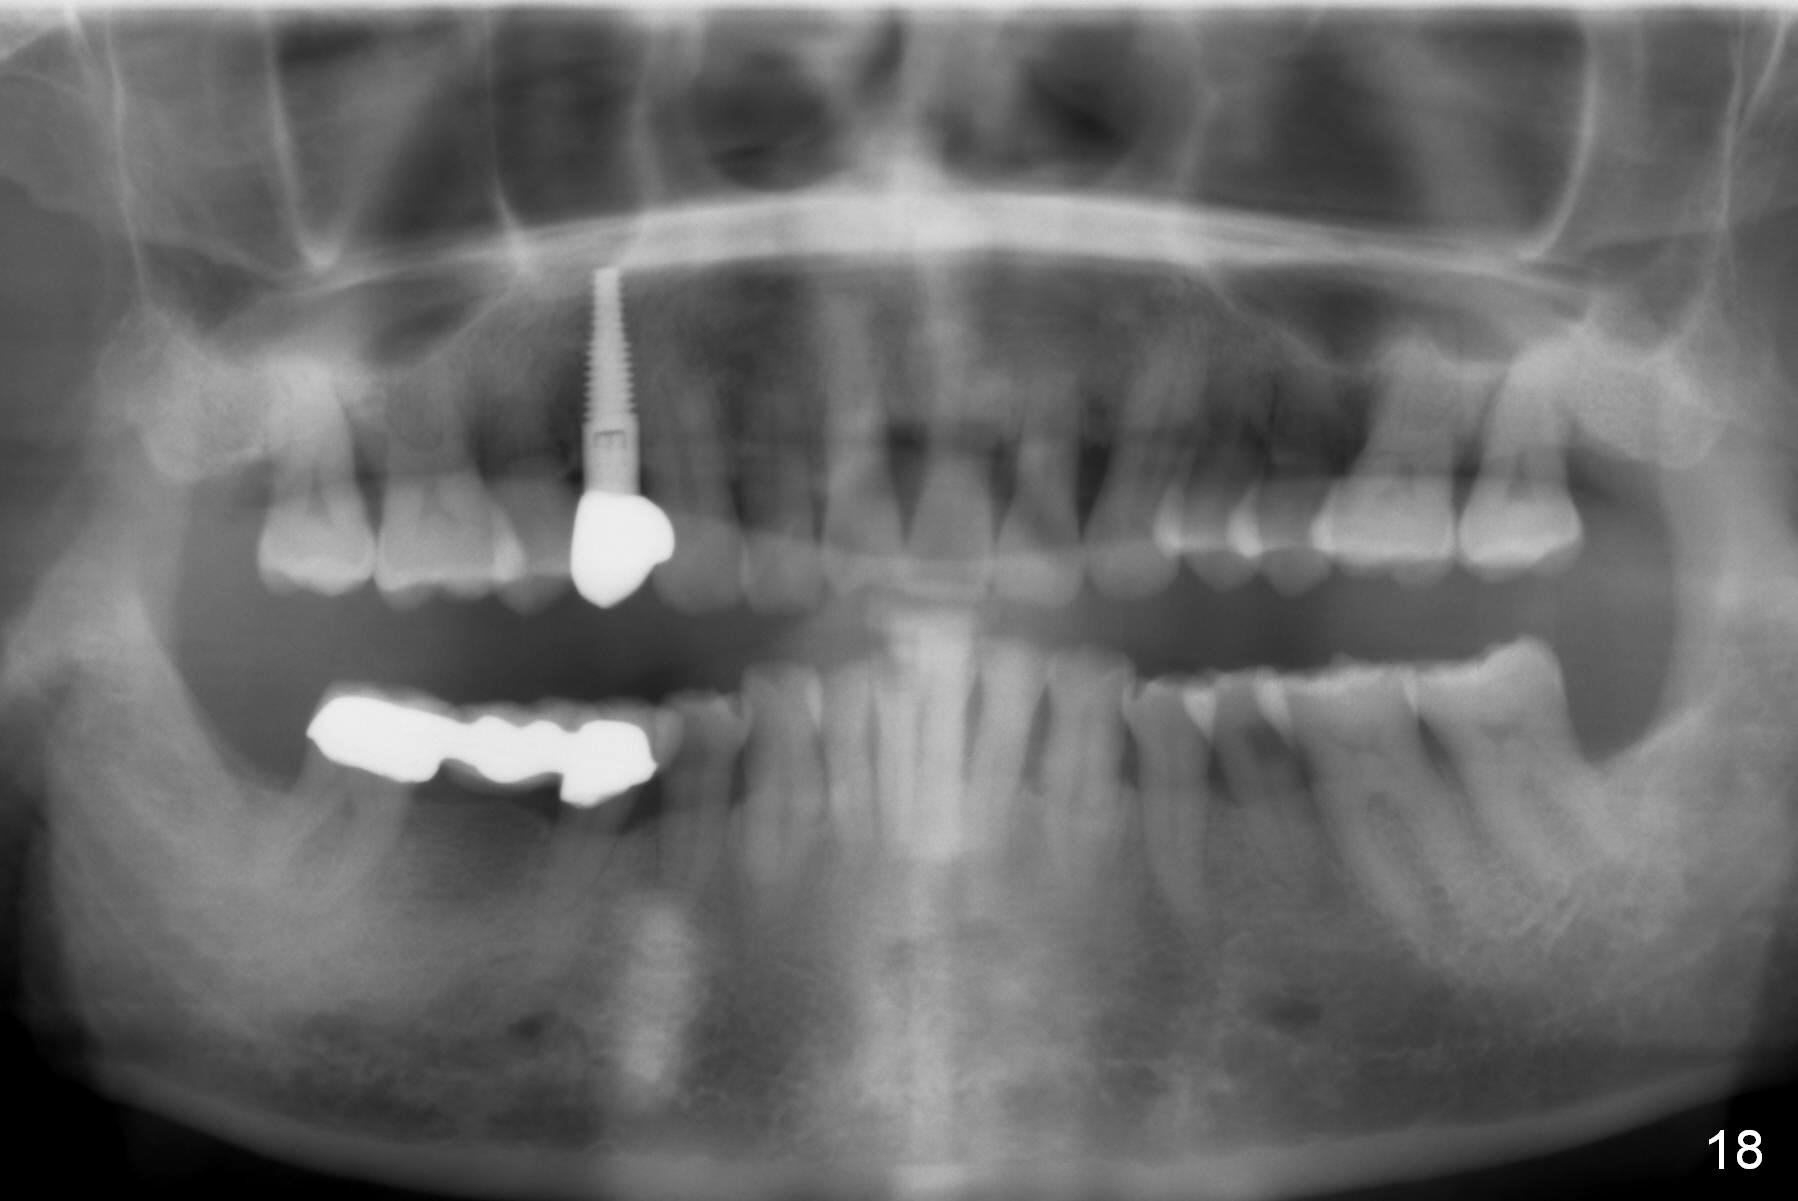

The long implant seems to be appropriate for the patient with periodontitis and bruxism (Fig.18, 2 years, 10 months post cementation). The implant appears to be placed buccally (B, Fig.19,20 (CBCT coronal and axial sections), 4 years, 5 months post cementation).